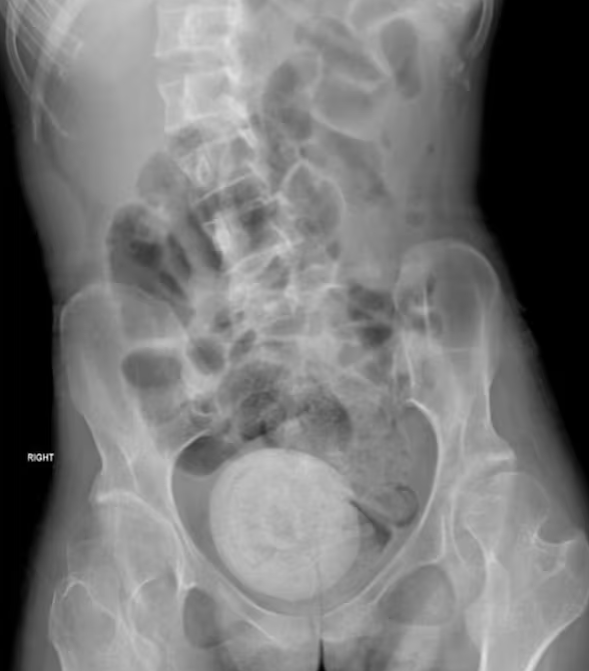

Mit Fieber und Erbrechen präsentierte sich die junge Dame dem medizinischen Team, ahnungslos über die bizarren Entwicklungen in ihrem eigenen Körper. Nach intensiven Untersuchungen kam die schockierende Diagnose ans Licht: Ein Vaginalstein, so groß wie eine Orange, hatte sich im Körper der Patientin gebildet.

Vaginalsteine sind äußerst selten und werden oft mit den gebräuchlicheren Nieren- oder Blasensteinen verwechselt. In diesem Fall jedoch überraschte nicht nur die Seltenheit, sondern auch die gewaltige Größe des Steins. Ärzte berichten, dass dieser durch die Stauung von Urin in der Vagina entstanden sei. Die junge Frau, die bereits unter einer Muskelerkrankung und Inkontinenz litt, begünstigte damit die ungewöhnliche Bildung des Vaginalsteins.

Die medizinische Intervention war dringend erforderlich, da ein solcher Stein im schlimmsten Fall zu Nierenversagen führen kann. Mithilfe eines Lasers wurden die neun mal zehn Zentimeter großen Brocken zunächst zerstört. In einer dreistündigen Operation wurden dann die Fragmente erfolgreich entfernt.